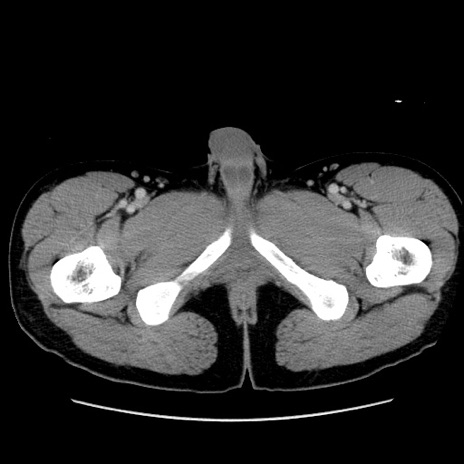

症例36(横断像)

【症例】20歳代 男性

【主訴】心窩部痛

【現病歴】今朝より上腹部痛あり。一旦軽快していたが再度出現したため救急要請。昨日夕に白身の魚を含む刺身を食べた。

【身体所見】BP 136/89mmHg、HR 74/min、BT 37.0℃、腹部:膨満、軟、心窩部に圧痛あり。反跳痛なし、筋性防御なし、腸雑音やや亢進あり。

【データ】WBC 17700、CRP 0.48